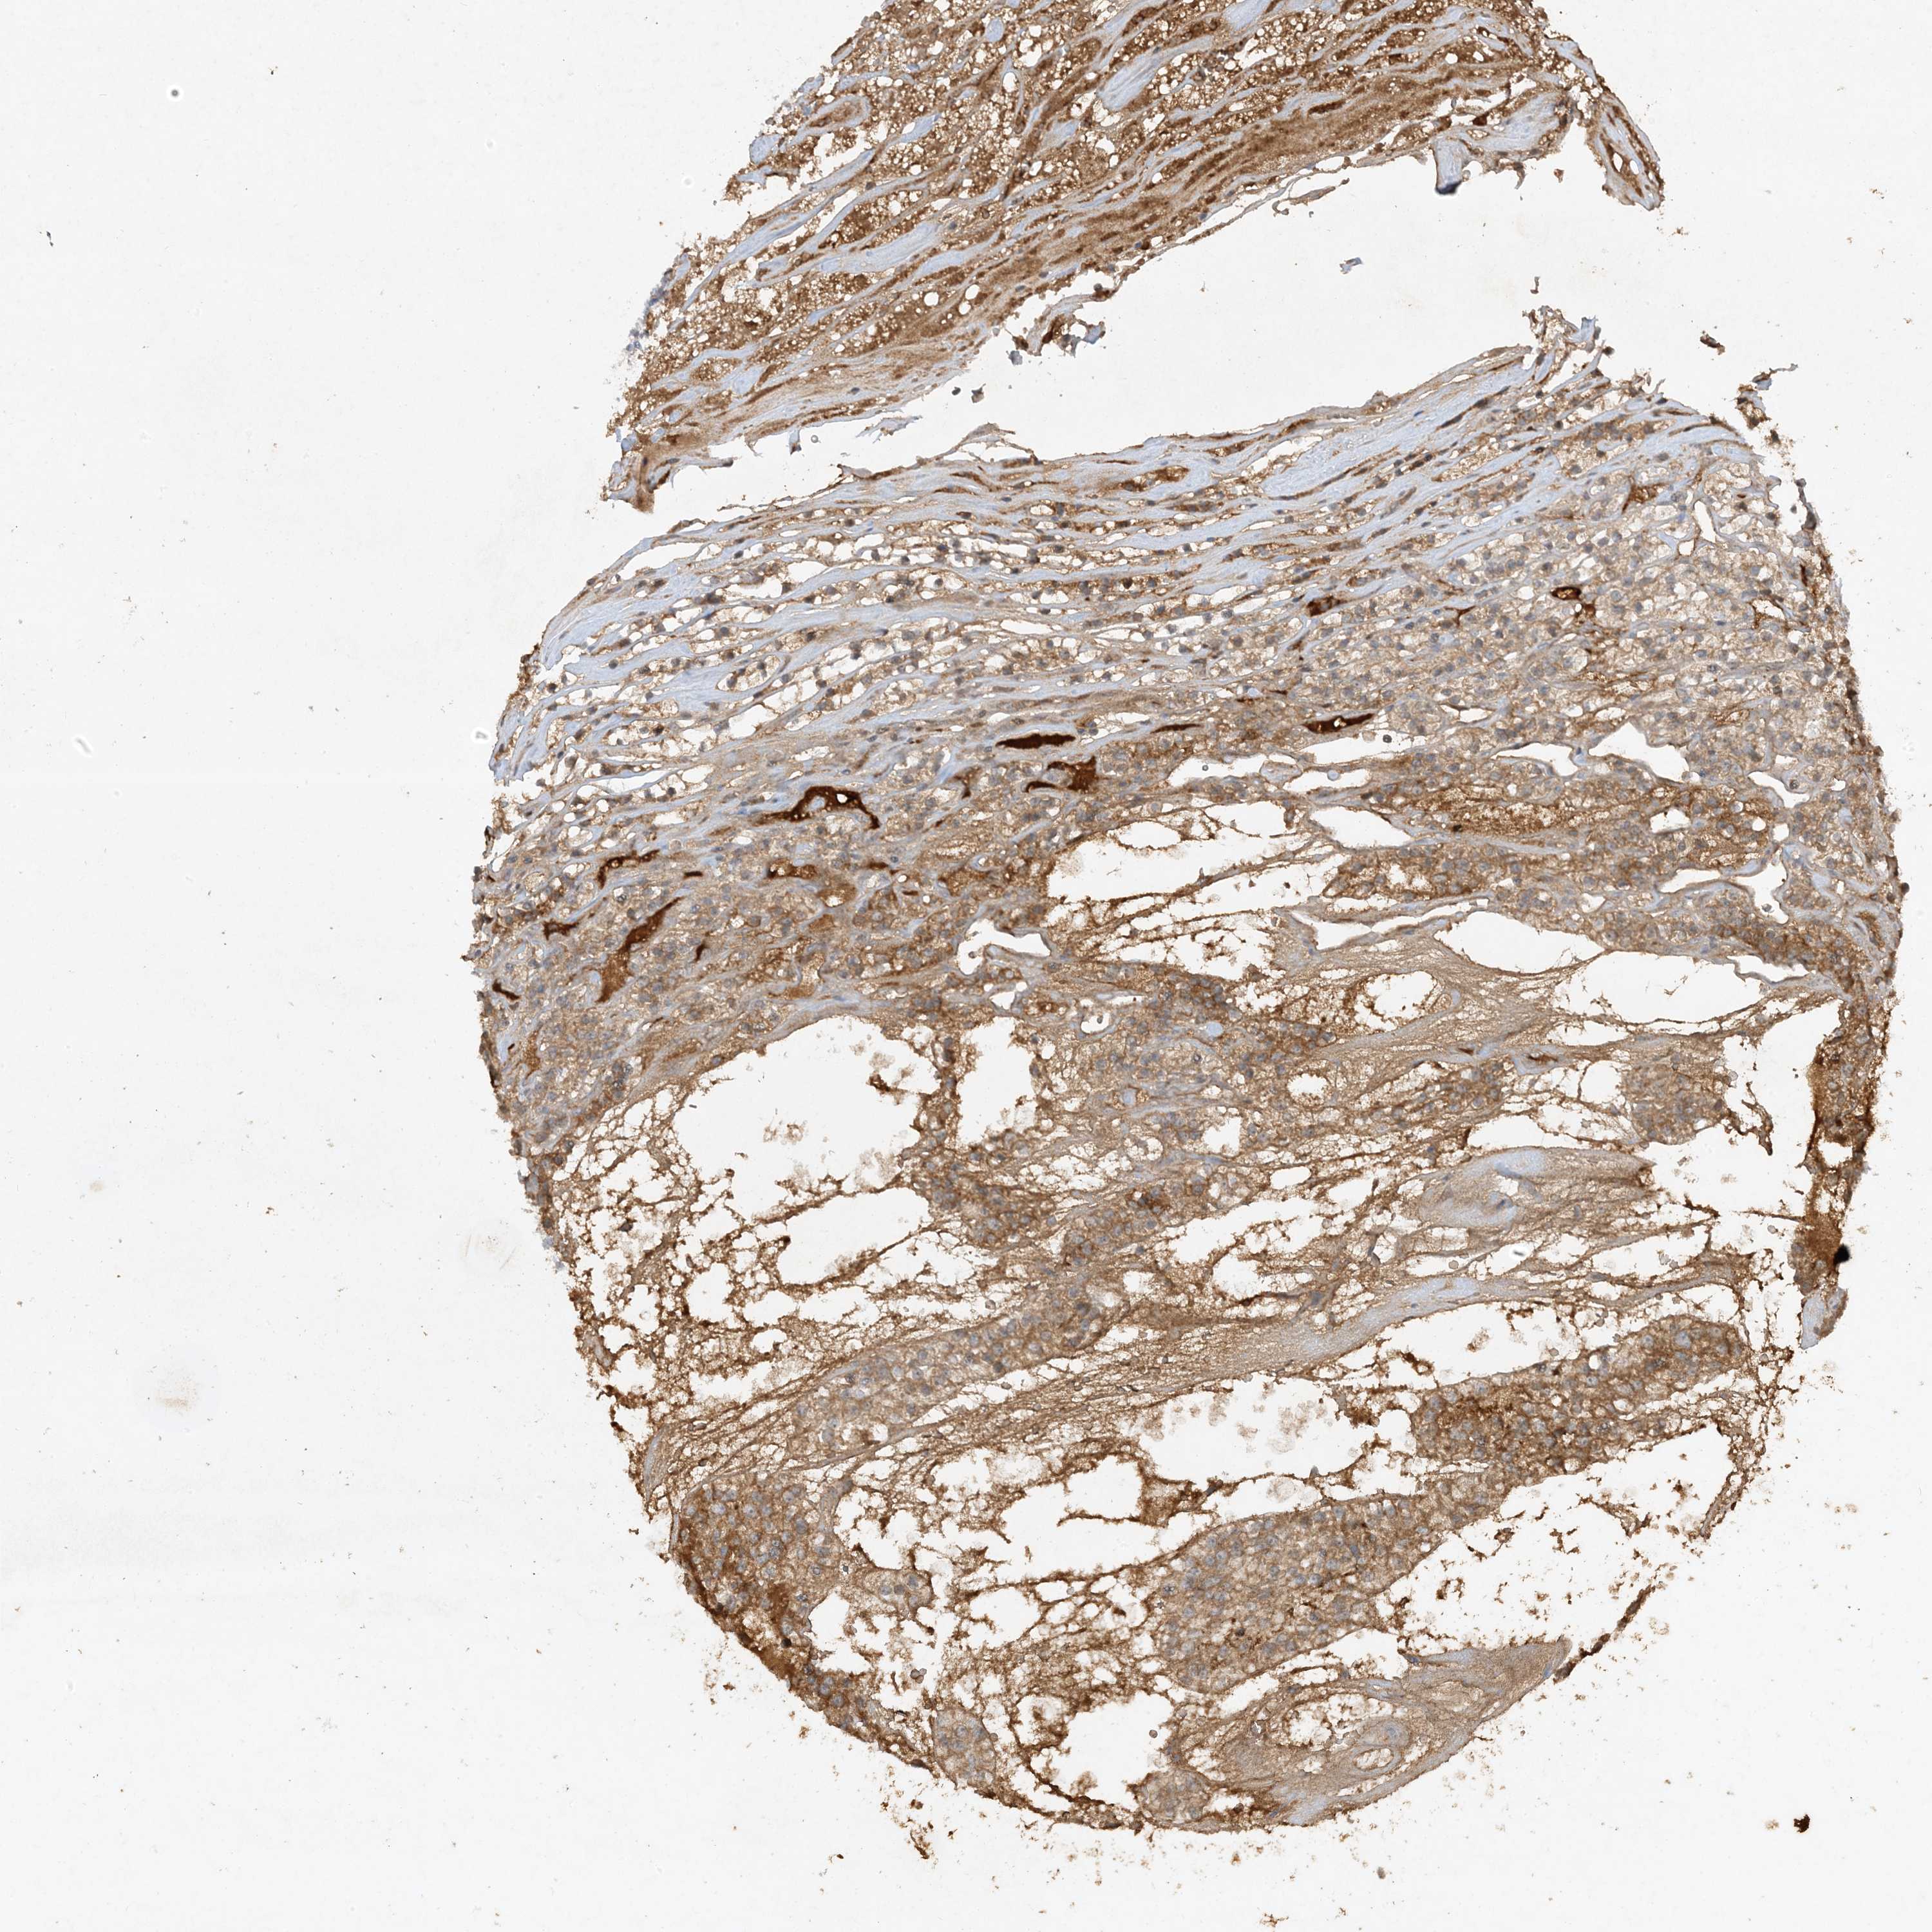

KIDNEY RENAL CLEAR CELL CARCINOMA (VALIDATION) - Interactive survival scatter ploti

The Survival Scatter plot shows the clinical status (i.e. dead or alive) for all individuals in the patient cohort, based on the same data that underlies the corresponding Kaplan-Meier plots. Patients that are alive at last time for follow-up are shown in blue and patients who have died during the study are shown in red.

The x-axis shows the expression levels (FPKM) of the investigated gene in the tumor tissue at the time of diagnosis. The y-axis shows the follow-up time after diagnosis (years). Both axes are complimented with kernel density curves demonstrating the data density over the axes. The top density plot shows the expression levels (FPKM) distribution among dead (red) and alive patients (blue). The right density plot shows the data density of the survived years of dead patients with high and low expression levels respectively, stratified using the cutoff indicated by the vertical dashed line through the Survival Scatter plot. This cutoff is automatically defined based on the FPKM cutoff that minimizes the p-score. The cutoff can be changed by dragging the vertical line or by entering a cutoff value in the square labeled "Current cut-off".

Under the Survival Scatter plot the p-score landscape (black curve; left axis) is shown together with dead median separation (red curve; right axis). Dead median separation is the difference in median mRNA expression between patients who have died with high and low expression, respectively. It is calculated as follows: median FPKM expression of dead patients with high expression - median FPKM expression of dead patients with low expression. This is intended to aid the user in visually exploring custom cutoffs and the associated p-scores and dead median separation.

Individual patient data is displayed and can be filtered by clicking on one or more of the category buttons on the top of the page. Categories describing expression level and patient information include: high, low, alive, dead, female, male and tumor stages. The scale of the x-axis can be toggled between linear and log-scale by clicking on the "x log" button. Mouse-over function shows TCGA ID, patient information and mRNA expression (FPKM) for each patient.

& Survival analysisi

Kaplan-Meier plots summarize results from analysis of correlation between mRNA expression level and patient survival. Patients were divided based on level of expression into one of the two groups "low" (under cut off) or "high" (over cut off). X-axis shows time for survival (years) and y-axis shows the probability of survival, where 1.0 corresponds to 100 percent.

Survival analysis data not available.

TCGA RNA samplesi

RNA-seq data is reported as average FPKM (number Fragments Per Kilobase of exon per Million reads), generated by the The Cancer Genome Atlas (TCGA) .

Normal distribution across the dataset is visualized with box plots, shown as median and 25th and 75th percentiles. Points are displayed as outliers if they are above or below 1.5 times the interquartile range. FPKM values of the individual samples are presented next to the box plot.

Average pTPM 0.1

Number of samples 100